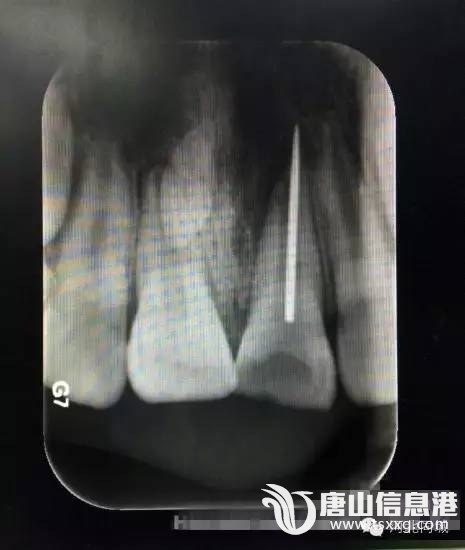

该院牙体二科任宏宇医生接诊后,结合牙片发现这名小男孩左上门牙根管里扎有一根断针。孩子牙龈红肿疼痛,烦躁不安,家长十分着急。

淘淘说,自己拿着妈妈的缝衣针给门牙里的牙洞“挠痒痒”,可玩着玩着针就断了,半截针扎进了门牙里。医生随即施以显微镜下根管异物取出术。10几分钟后,一根2厘米左右的断针从孩子的左上门牙根管里顺利取出。原来,孩子嘴里这颗扎进断针的牙齿是有龋洞的龋齿,孩子玩针时才误将钢针扎进牙的根管里。